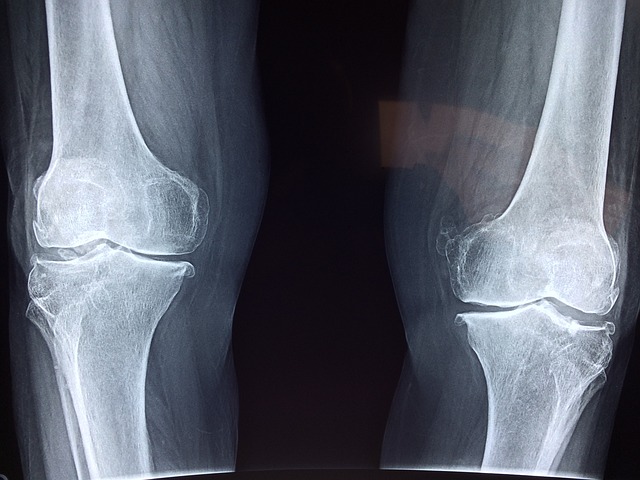

날씨가 추워 지면서 근육이 경직되거나 아프던 무릎이 더 악화 되는 경우가 어르신분들이 많으시더라구요

무릎관절증으로 조속적인 통증에 시달리거나 경제적 이유로 수술을 받지 못하는 노인들의 고통을 경감하여 싦의 질을 개선

무릎 인공관절 수술비 지원대상 지원범위

나이 : 만60세 이상

지원대상 : 기초생활수급자, 차상위계층, 한무보가족등, 저소득층 어르신

지원범위 : 무릎인공관절수술비와 관련된 검사비, 수술비, 진료비